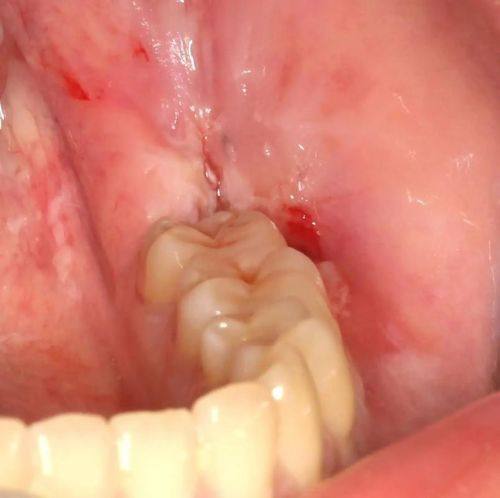

拔牙:包括智齿拔除等各类拔牙项目,术后护理指导到位,保护术后修复顺利。

北京朝阳佳美口腔(三里屯店)智齿拔除:500元起/颗

“我长了阻生智齿,疼了好长时间,朋友推荐来这家店拔牙。医生术前跟我详细讲解了拔牙方案,缓解了我的紧张情绪,拔牙过程比我预想的轻松特别多,术后还特意给了详细的护理注意事项,现在修复得特别顺利,终于不用再受智齿疼的困扰了!”